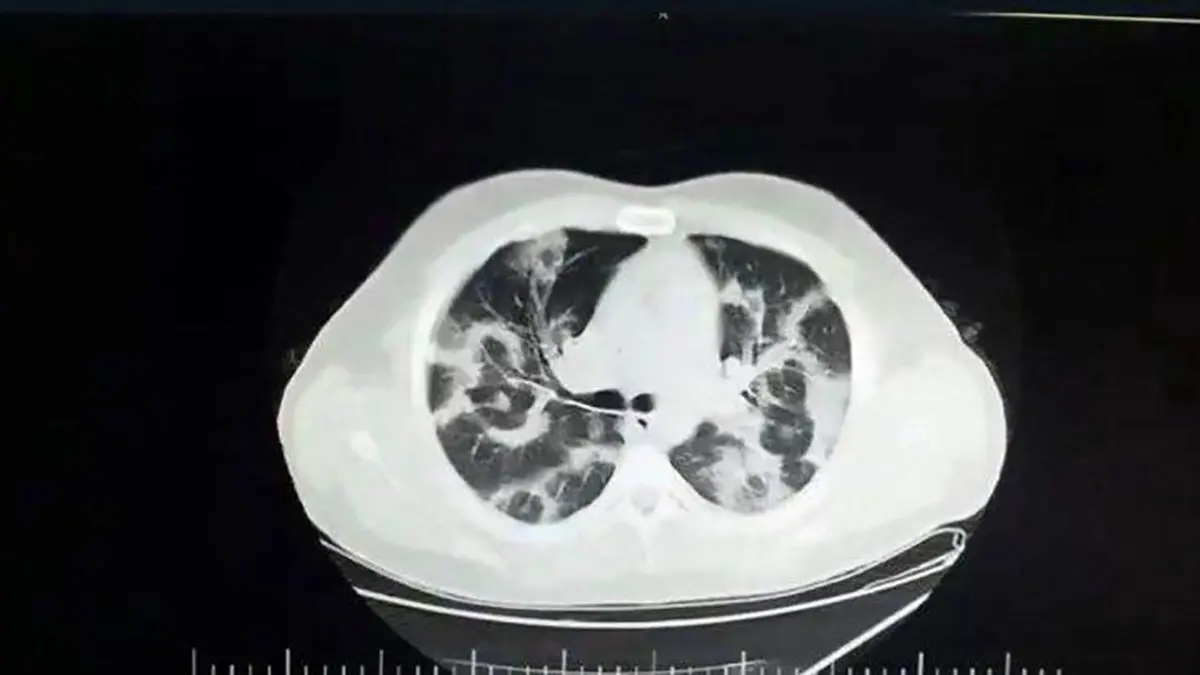

اولین عکس از ریه کرونایی انگلیسی / هشدار برای زیر 20 ساله ها!

کرونای انگلیسی جهش یافته افراد سن پایین را درگیر می کند و در سی تی اسکن بیماران جوان مبتلا به کرونای انگلیسی ریه های بلافاصله درگیر می شود و بعد از 3 روز فرد دچار علامت خواهد شد.